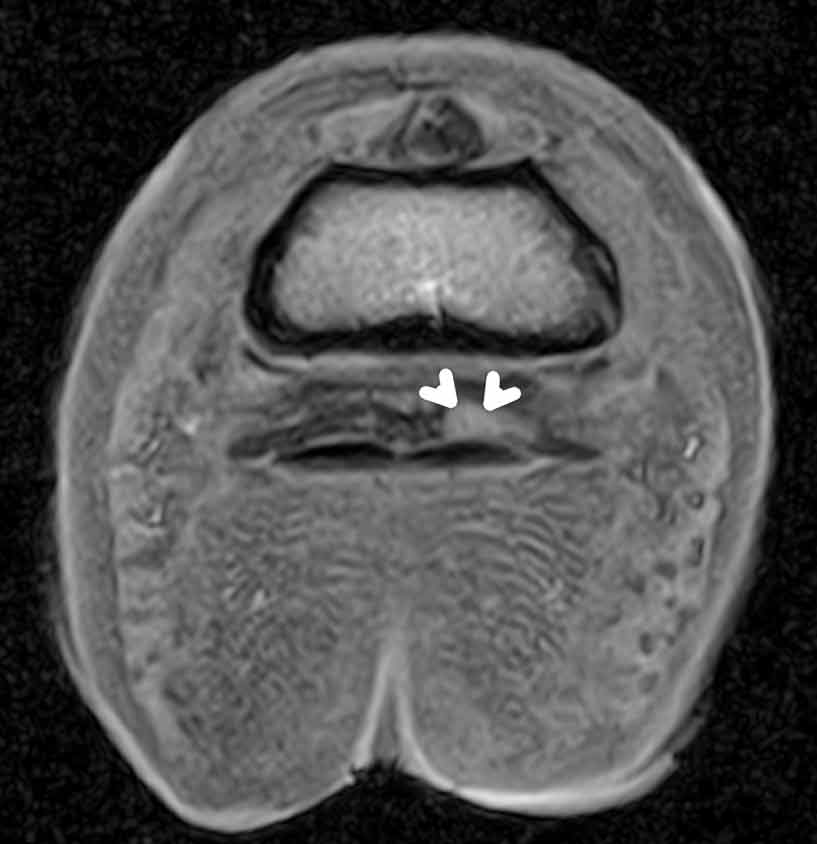

Figure 1. Transverse T1W gradient echo (GRE) and T2W fast spin echo images of the foot. The white arrows indicate a focal deep digital flexor tendon lesion and the red arrows indicate effusion of the navicular bursa.

The major benefits of MRI are it allows for identification of soft tissue lesions – for example, those affecting the deep digital flexor tendon within the hoof capsule, one of the most commonly injured structures. With identification comes the ability to classify the lesion into varying types (core, dorsal border, parasagittal split, insertional lesion) and the extent of the abnormal region. This also allows for identification of involvement of the adjacent structures, such as fibrillation of torn tendon fibres into the navicular bursa (Figure 1), or potential adhesion formation associated with torn tendon fibres to the collateral sesamoidean ligament or navicular bone.